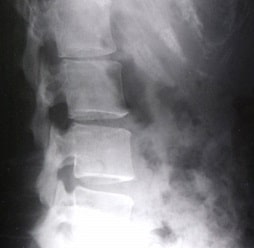

一般的な整形外科では腰痛、腰下肢痛などの場合レントゲンを撮り画像を参考に治療を進めていきます。

さらに詳しく検査する場合、CT・MRIなどの検査がおこなわれます。

画像検査で異常が認められた場合、ほとんどのケースでは、その異常が腰痛やしびれ等の症状の原因とされてしまいます。

実は、脊柱管狭窄症や椎間板ヘルニアが画像診断では認められても、全く症状が無く普通に生活をしている方がたくさんおられるのも事実です。

極度の腰痛で脊柱管狭窄症や脊椎ヘルニアと診断されて手術された方が一時的に痛みが軽減しても、腰痛を繰り返す原因は画像からのみの判断では十分でないことを証明しています。

例えば画像に映っている筋肉が緊張しているか否かは画像のみの判断では大変難しく、もしその一部の筋肉が神経根周辺を圧迫していた場合、いくら手術をして、問題だとしてしまっている構造を再構築しても、痛みはなかなか治まりません。

神経学的検査を行ったうえで単純X線撮影や血液検査など基本的な検査はひととおり行うべきとされています。その結果、あきらかな疾患をみいだしたならば、その疾患に最適な治療法を選択します。

一方、X線撮影やMRIなどで著しい変形性脊椎症や軽度の奇形を発見しても、それが腰痛の原因として意味ある所見なのかどうかは慎重に考えるべきとされています。